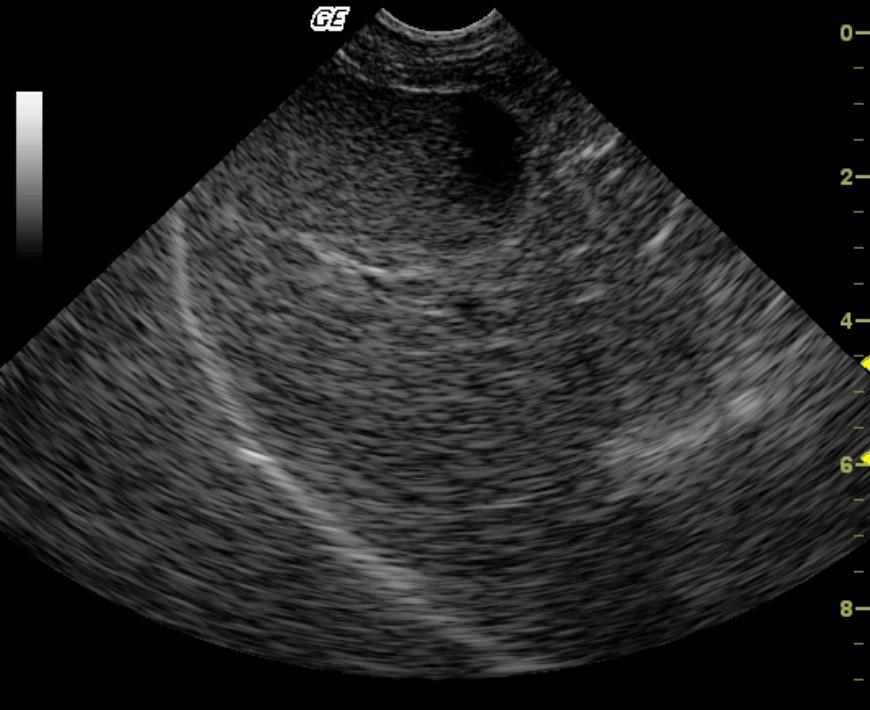

The liver parenchyma was coarse with increased portal markings. The gall bladder presented minor excessive debris with echogenic wall.

Chronic inflammatory hepatopathy with fibrosis potentially hypomotile gall bladder.

Chronic suppurative cholangiohepatitis with portal fibrosis and parenchymal collapse.

Ultrasound guided biopsy of the liver revealed a chronic suppurative cholangiohepatitis with portal fibrosis and parenchymal collapse.